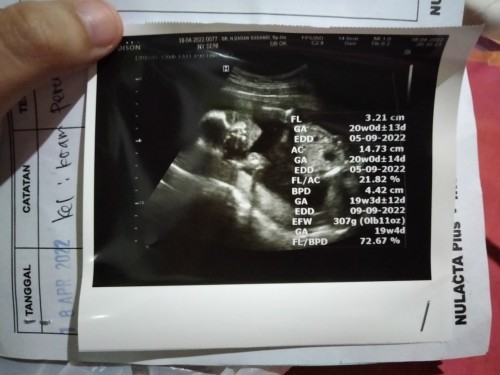

Apakah hasil USG usia 20 Minggu(5bulan) ini tolong artikan setiap apa itu FL dll? Apakah normal,,

bisa googling aja keywordnya "cara membaca hasil usg". saya bantu jawab FL nya aja, sisanya baca sendiri ya dr hasil googling. FL itu femur length, panjang tulang paha. artinya paha janin ibu panjangnya 3.21cm, seukuran paha janin usia 20w, hpl dr usia tsbt 5 sept 22. dikatakan normal kalo semua ukuran & hpl nya sesuai dgn usia & hpl yg seharusnya. skrg hrsnya 20w? brrti ukuran paha janin ibu sesuai, normal